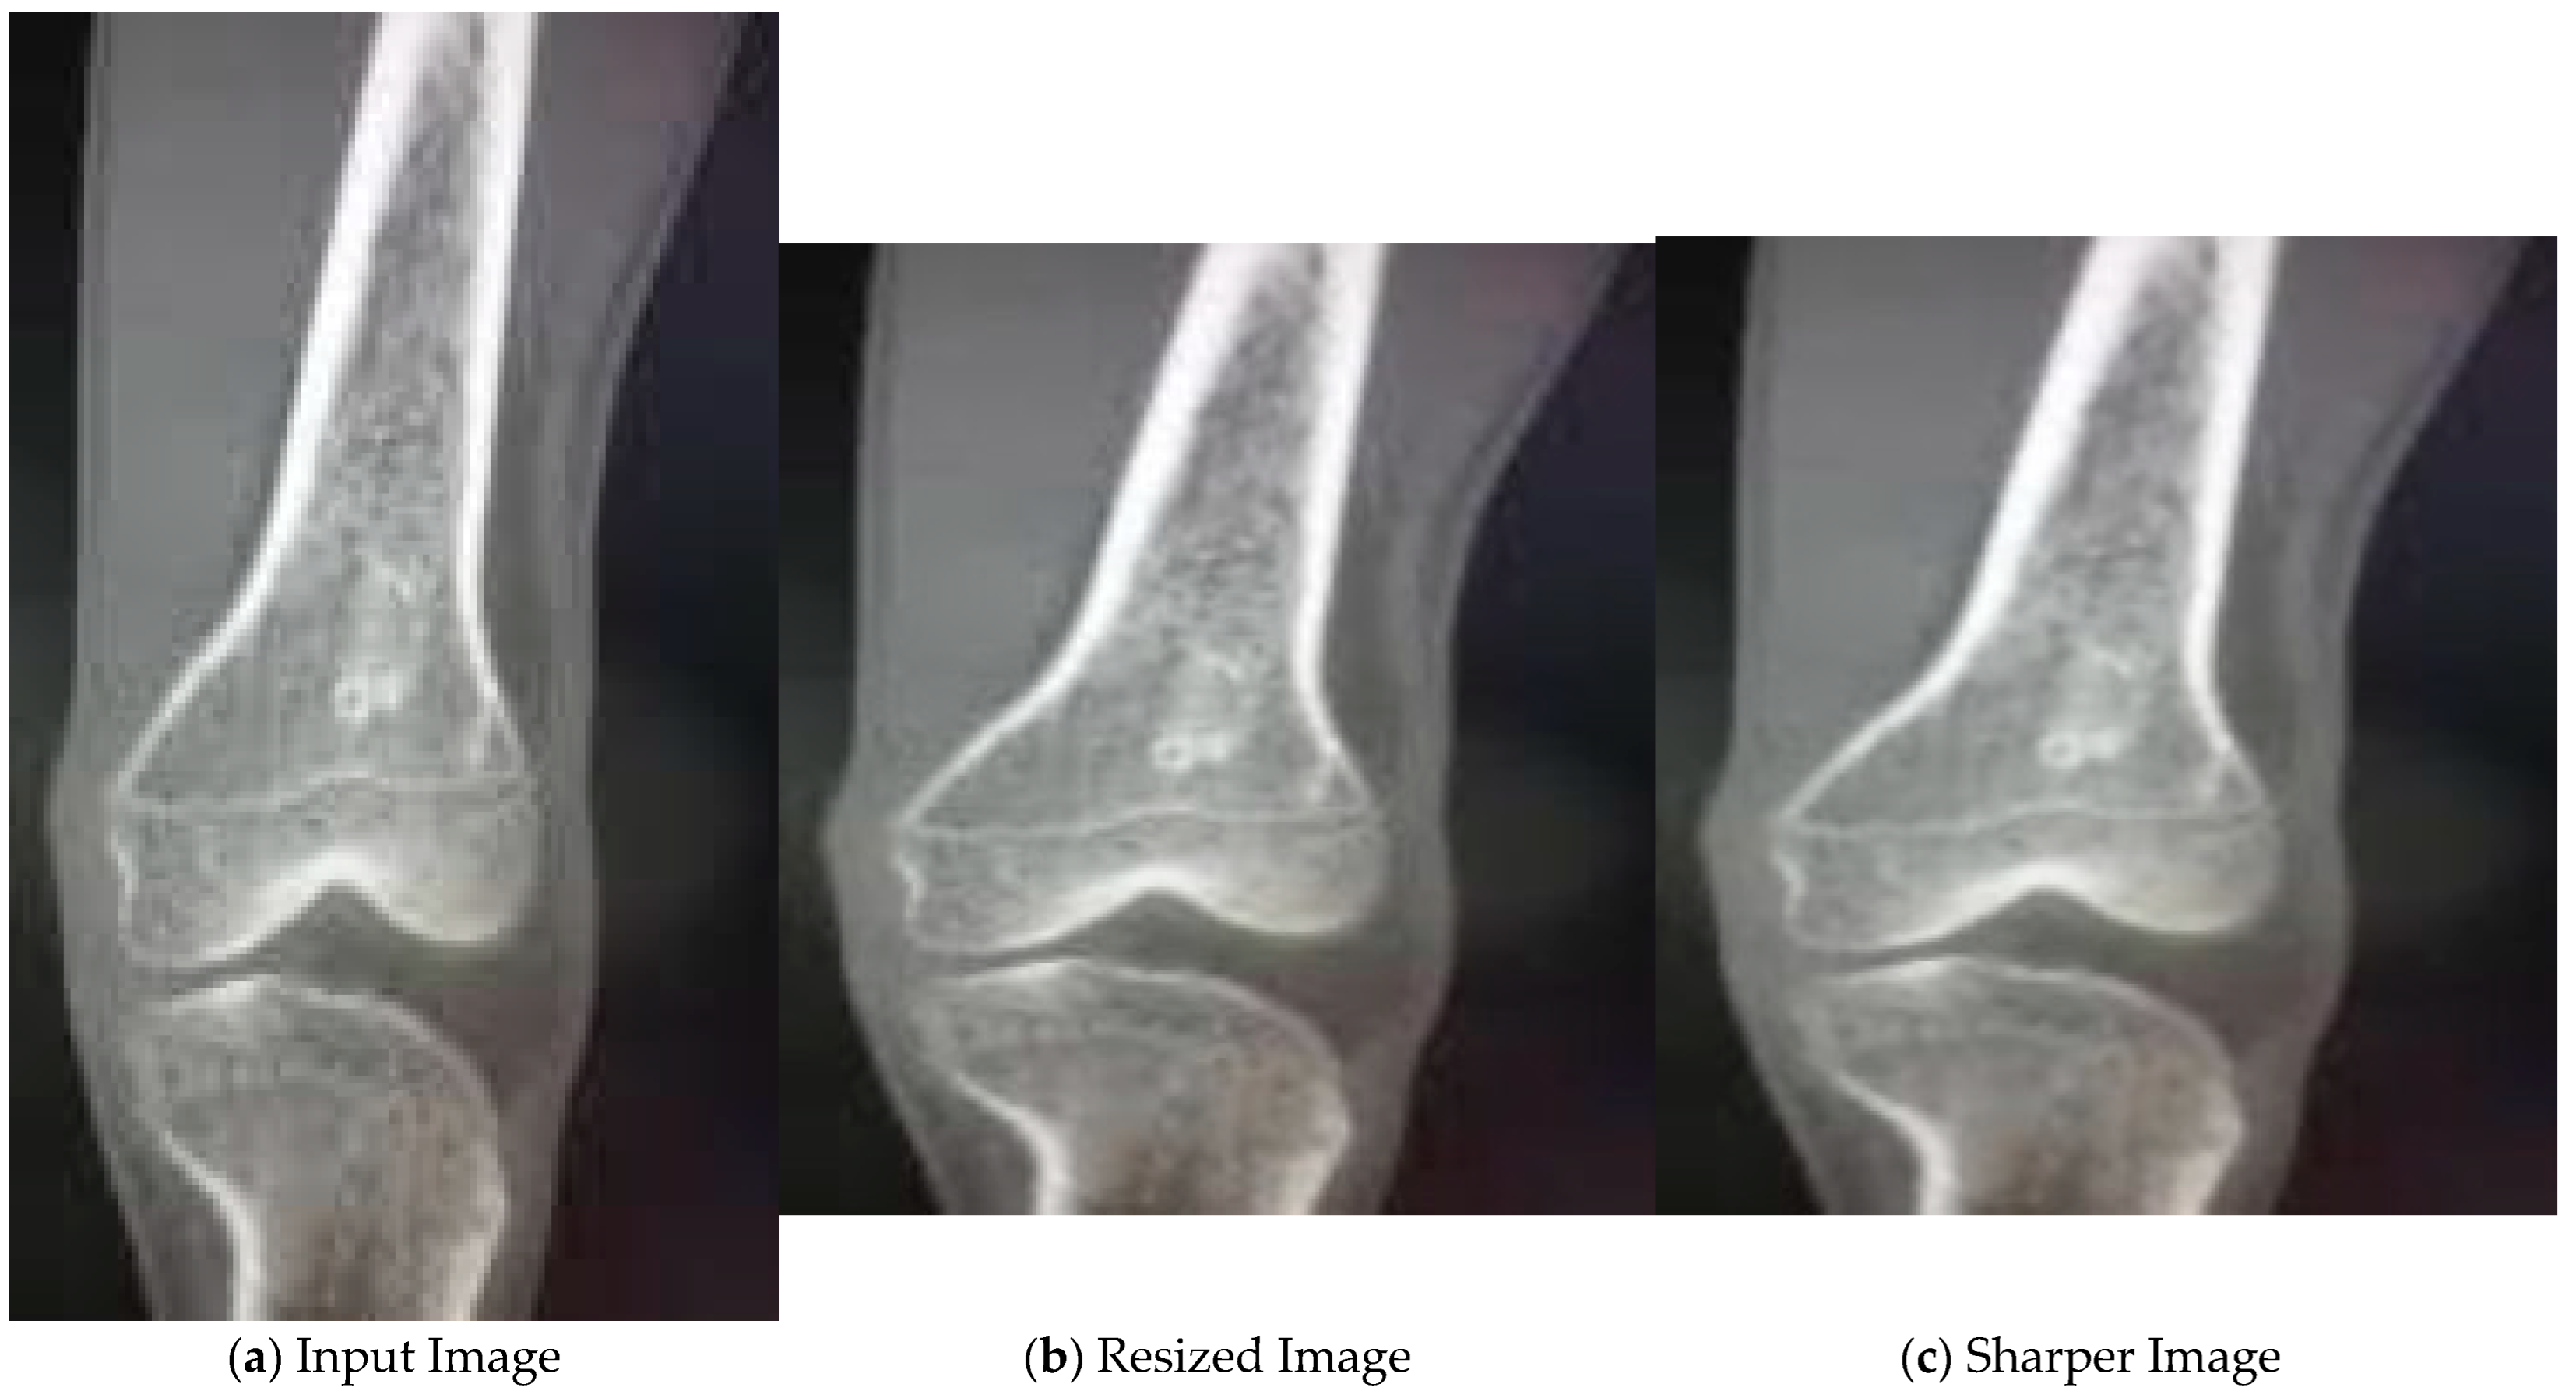

4.2. Results for Pre-Processing

In the initial stage, the input image, as shown in Figure 4a, is resized. Then, median filter is applied to the resized image as seen in Figure 4b. As a result, we get a sharper image, as shown in Figure 4c, with reduced noise.

Figure 4.

Pre-processing of X-ray images.